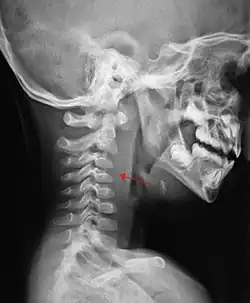

The retropharyngeal space (abbreviated as "RPS"[1][2]) is a potential space[2][3] and deep compartment of the head and neck[1] situated posterior to the pharynx.[4] The RPS is bounded anteriorly by the buccopharyngeal fascia, posteriorly by the alar fascia, and laterally by the carotid sheath. It extends between the base of the skull superiorly, and the mediastinum inferiorly.[1] It contains the retropharyngeal lymph nodes.[2] Its function is to facilitate movements in the superoinferior axis of the larynx, pharynx, and esophagus in relation to the cervical spine.[3]

If more than half of the size of the C2 vertebra, it may indicate retropharyngeal abscess.[7]